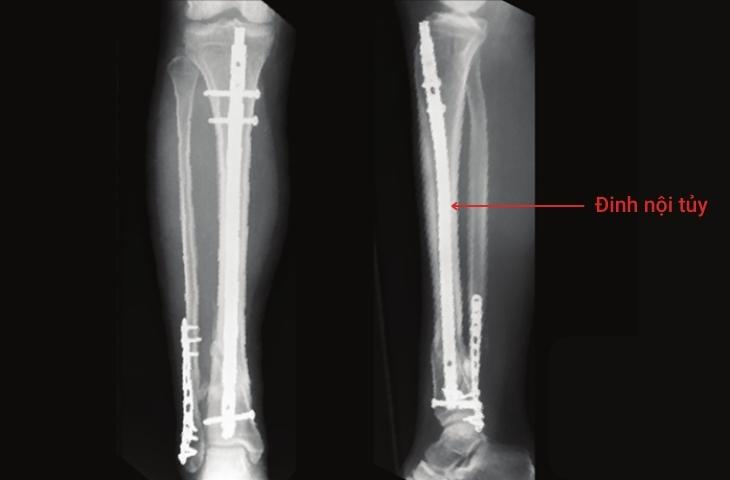

Phẫu thuật kết hợp xương sinh học bằng đinh nội tủy

Phẫu thuật kết hợp xương sinh học bằng đinh nội tủy thường được chỉ định cho bệnh nhân gãy từ 1/3 thân xương chi dưới, đặc biệt là các xương ống dài như xương đùi, xương chày... vì đinh nội tủy có khả năng chịu lực tỳ lớn trong khi chi dưới phải gánh trọng lực lớn khi cơ thể vận động, đi lại.

phẫu thuật kết hợp xương sinh học Phẫu thuật kết hợp xương sinh học sửu dụng đinh luồn vào trong ống tủy.

Kết hợp với bàn mổ chỉnh hình, màn tăng sáng C-arm, bác sĩ chỉ cần rạch da khoảng 3-4 cm để luồn đinh vào ống tủy rồi chốt ở hai đầu. Thủ thuật này giữ đinh và xương được nằm đúng vị trí trong quá trình liền xương, cố định vững chắc và ổn định toàn bộ chiều dài xương. Nhờ thế, hạn chế tối đa tổn thương phần mềm, bệnh nhân ít bị mất máu, ít đau, giảm nguy cơ nhiễm trùng và nhanh liền xương.